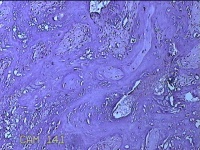

胎盘组织

性别

女

年龄

30岁

临床诊断

妊娠合并中度贫血

一般病史

停经39+2周,B超检查发现羊水偏少6小时。

标本名称

大体所见

灰白暗红色胎盘组织16.5x14.5x3.5㎝一个,表面光滑,血管突出,颜色发暗,绒毛面结节状,有轻度糜烂,暗红色,有少许凝血块,切面见绒毛内有暗红色血液渗出,边缘蜕膜可见多个小血肿,脐带39x1.8x0.3㎝,螺旋状扭曲,切断脐带,见脐血管内有凝血块。